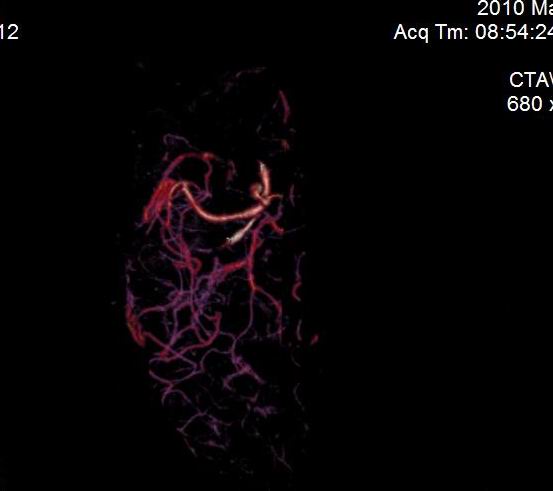

男.60岁,渐进性意识不清,ct检查双侧额颞顶部硬膜下血肿,开颅术后行脑血管cta,大脑中动脉起始部见一瘤状血管扩张。请各位老师留下宝贵意见

后重建做得不是很好看,要将维蒂斯环充分显示,最好在增加一个mip。这样不好定位。